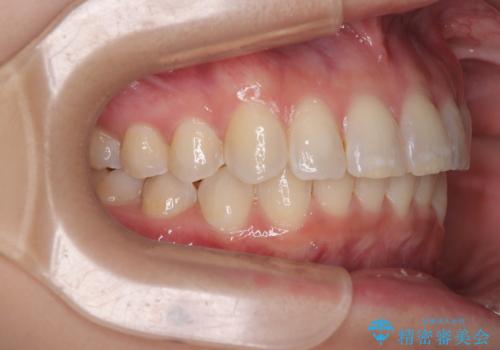

なかなか舌の突出癖が改善できず、上下前歯が非接触となる期間が長く続きました。

アンカースクリューの活用と、舌のトレーニングを何度も指導し、出っ歯になることなく無事に治療を終えることができました。